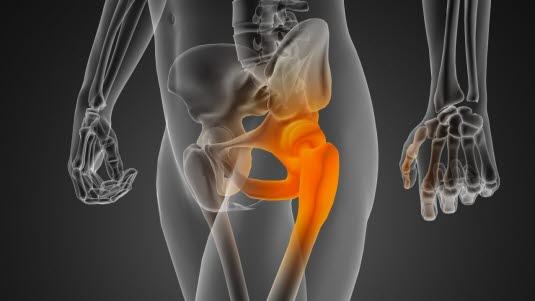

Bekkenet med hofteleddHofteleddet er et kuleledd som består av leddkule (lårbeinshodet) og leddskål (acetabulum). Leddflatene til lårbeinshodet og acetabulum er kledd med leddbrusk. Hofteleddet har en betydelig bevegelighet i alle plan og stabiliseres av leddkapselen, omgivende muskler, bruskskålen som kler den benede leddskålen og en bruskkant (labrum) som forlenger bruskskålen og stikker noen millimeter ut over den beinede kanten av hofteskålen. Labrum gjør dermed leddskålen dypere, gjør leddet stødigere og beskytter leddet.

Bruskskade oppstår i grenseflaten mellom lårbeinshodet og kanten på bruskskålen. Det skilles mellom to hovedtyper skader: Skader på labrumbrusken og skader eller forandringer på lårbeinshodet. Slike bruskskader fører til at små fliker av brusk stikker ut og kan komme i klem - derav navnet impingement eller innklemming. Det er en tilsvarende skade som oppstår i kneleddet ved meniskskade.